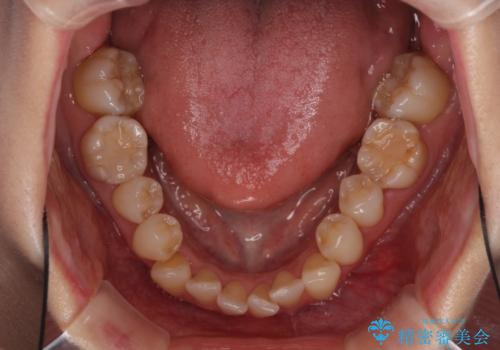

- 奥歯の咬み合わせを気にして来院された患者様です。

上顎骨の幅が下顎骨よりも小さいので、拡大装置により骨幅を広げて上下関係を改善し、その後インビザラインにて歯並びを整えることとしました。

上下の骨幅を改善したことで、スムーズに歯列矯正を行うことができました。

奥歯の咬み合わせを改善する必要があったため、治療は長期化しましたが、きっちりと仕上げることができました。